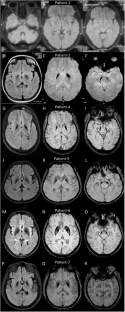

Mitochondrial membrane protein-associated neurodegeneration (MPAN) is a rare neurodegenerative disorder characterized by spastic paraplegia, parkinsonism and psychiatric and/or behavioral symptoms caused by variants in gene encoding chromosome-19 open reading frame-12 (C19orf12). We present here seven patients from six unrelated families with detailed clinical, radiological, and genetic investigations. Childhood-onset patients predominantly had a spastic ataxic phenotype with optic atrophy, while adult-onset patients were presented with cognitive, behavioral, and parkinsonian symptoms. Levodopa induced choreiform dyskinesia was observed in one patient who showed a response to levodopa. Brain magnetic resonance imaging showed mineralization in all patients and cerebellar atrophy in one patient. The “pallidal splitting sign” was found in two patients and additional caudate and putamen mineralization was noted in two patients. Exome sequencing identified six variants in the C19orf12 gene, including two novel splice-site variants, four previously reported missense variants. Transcript analysis using RT-PCR followed by Sanger sequencing was performed on a splice site variant (c.194-2delA) to understand the splice defect and its consequences. This analysis confirmed the splice defect and use of an alternate cryptic splice site in the downstream exonic region. The variants identified in this study expand the spectrum of clinical and genetic knowledge on MPAN patients, highlighting the importance of genetic testing in the diagnosis and management of this disorder.